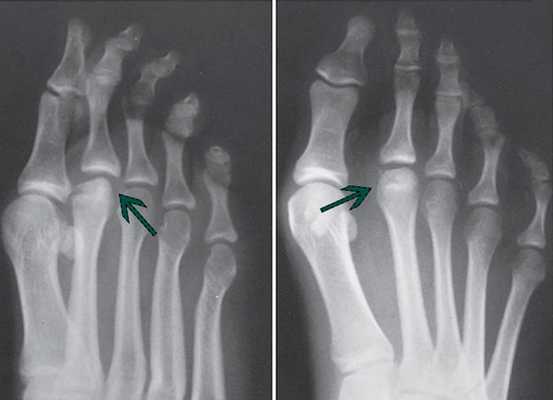

Рентгенологические признаки болезни Келлера. Ранние стадии заболевания характеризуются остеолизом и центральным коллапсом головки

III стадия характеризуется продолжающейся деформацией всей головки. Немного хряща остается на подошвенной поверхности головки.

В IV стадию формируются переломы измененной субхондральной кости, приводя к появлению в полости сустава свободных тел.

На V стадии головка плюсневой кости значительно уплощена и расширена, суставная щели сужена, появляются грубые вторичные артрозные изменения.

Рентгенологические признаки болезни Келлера. Поздние стадии заболевания: центральный коллапс и остеолиз головки.